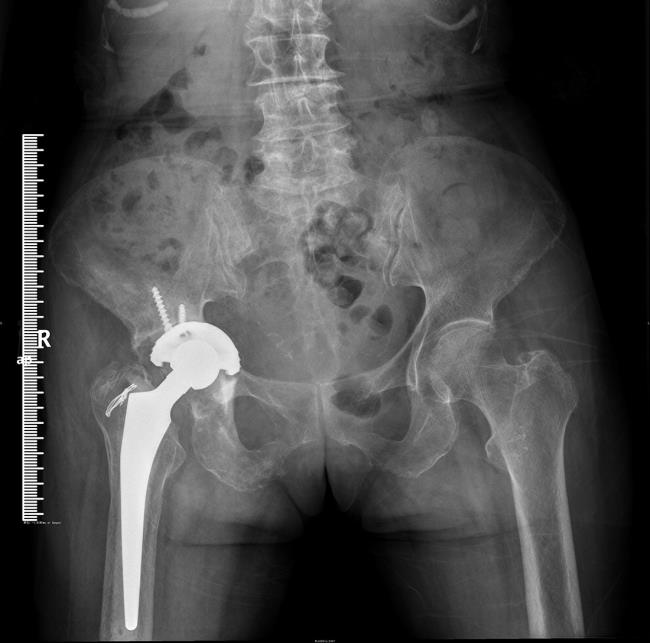

病例1:女,74岁,因右股骨颈骨折在外省某医院做人工全髋关节置换手术,术后由于右髋关节疼痛,活动障碍,严重影响生活,在床上敞了一年多,后转到我科治疗。

经我科行人工关节翻修手术,术后疼痛缓解,活动功能恢复,3个月后复查患者已能下地活动,效果满意。